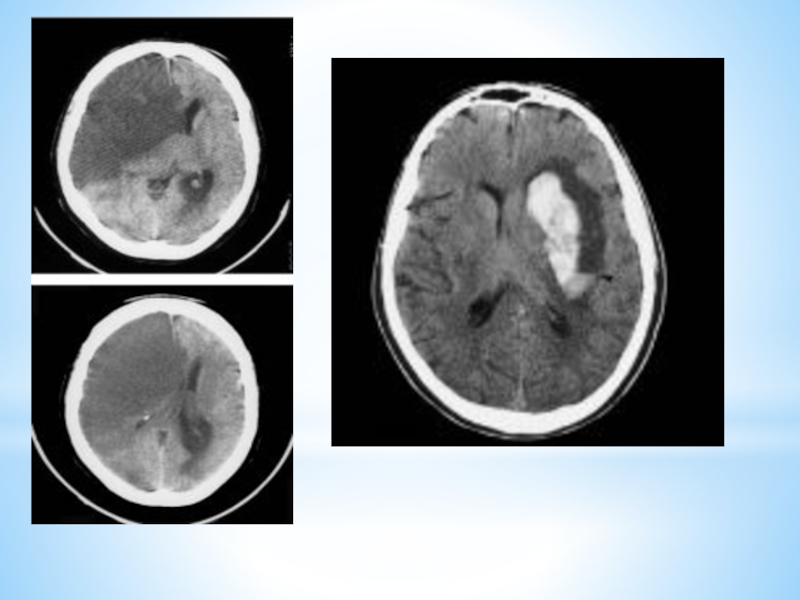

Слайд 14Диагностика

Компьютерная томография (КТ) и магнитно-резонансная томография (МРТ) — наиболее важные диагностические

исследования при инсульте, позволяющие определить размеры, локализацию поражения мозга, а

также определить вид инсульта (инфаркт или кровоизлияние)

Кроме того выполняются различные исследования для уточнения состояния различных систем организма, выявления сопутствующих заболеваний, которые могут привести к осложнениям в течении заболевания (ЭКГ, исследования крови, ультразвуковое исследование сосудов, рентгеновское обследование и др.)